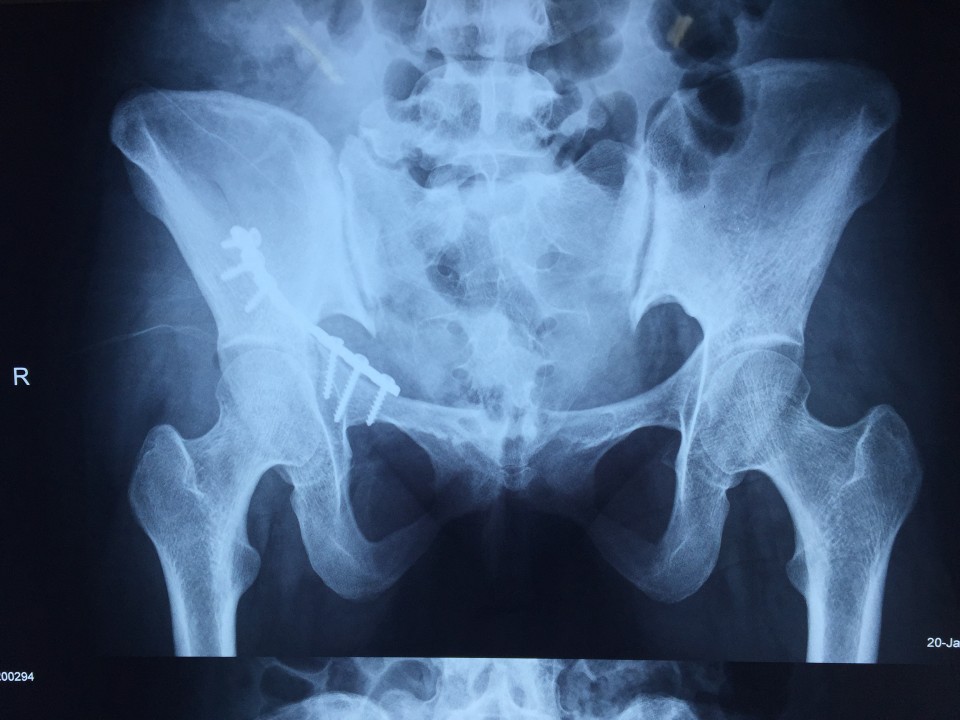

近日,我院创伤骨科七东利用改良Stoppa经腹白线旁入路成功治疗一例髋臼骨折患者。该患者女性,27岁,骨盆车祸伤。术前检查诊断为右侧髋臼骨折(AO分型为A3型)。该患者有剖宫产病史,腹部组织粘黏严重,手术难度较大。经过科室专家多次会诊,刘德宝主任制定详细手术方案,决定术中采用改良Stoppa入路,以减少手术创伤的影响。最终该手术顺利完成,历时一小时余,术中出血仅200ml,术后患者恢复良好。 采用改良Stoppa入路治疗髋臼骨折为安徽省首例,标志着我院创伤骨科进一步迈入创伤省内领先,国内先进的水平。

传统的对于髋臼前壁骨折的治疗方式主要为髂腹股沟入路,此入路内有重要的神经、血管经过,操作费时,术中可能导致股神经、血管及股外侧皮神经、精索或圆韧带的损伤。且骨折需通过3个窗口显露,骨折区域显露有限。针对髂腹股沟入路的缺点,我们使用改良Stoppa入路弥补了髂腹股沟入路的不足,它采用腹白线旁入路,推开腹膜内脏器,腹膜外达到真骨盆缘,一个窗口获得骨盆术野,可很好显露骨盆环。它有以下优点:此入路有宽阔的视野,并能直视骨盆缘,故可有效处理“死亡冠”,减少出血的发生;钢板塑形简单,钢板置入区域真骨盆内缘平坦,只需在一个平面预弯即可,并不需扭转钢板;可双侧骨盆缘复位固定,对于双侧耻骨上支及髋臼前柱骨折可轻易达到;术后病人康复快,因患者经下腹正中入路,并未损伤到髋部周围各层肌肉组织,故患侧肢体术后康复较快。据悉,此项技术在国内仅少数医院开展,在省内尚属首例。